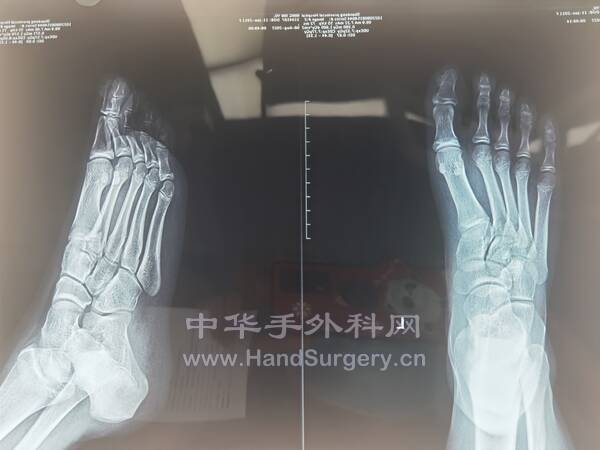

2.右跟骨闭合骨折切开复位钛板内固定术:取足跟外侧改良L形切口,逐层切开显露,剥离骨膜,显露骨折端,见距下关节变形,恢复跟骨高度,宽度及距下关节面,术中拍片示贝氏角,关节面角至正常范围,放置跟骨钛板1枚及螺钉9枚,逐层闭合切口,放置引流条2枚。